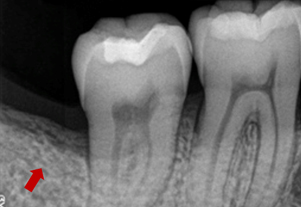

症例3(再生療法)

Before

After

- POINT

- 他院で歯周病の治療をしていましたが、なかなか歯周病が改善されず、セカンドオピニオンにて来院された患者様です。歯周病の進行した部分に再生療法を行い(エムドゲインを使った歯茎の手術)ホームケアを徹底することで改善されました。

今後も継続したメインテナンスが必要です。